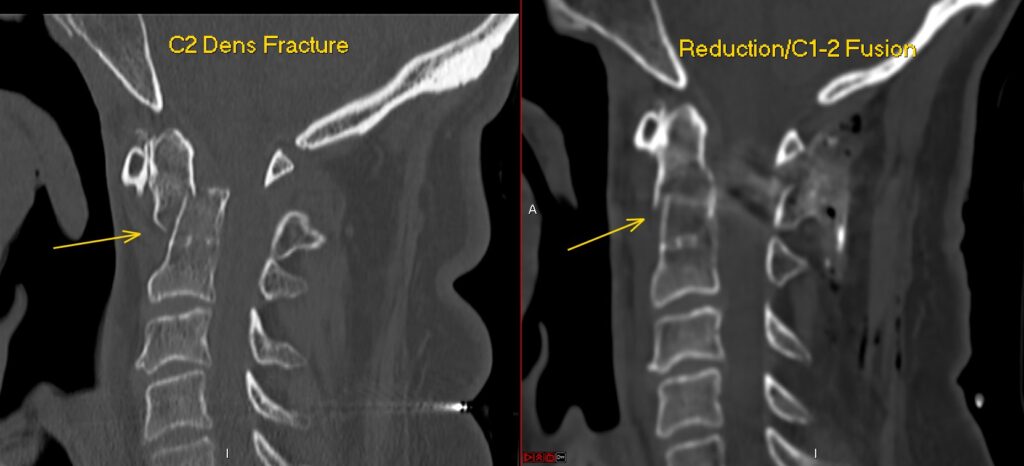

C1-2 fusion